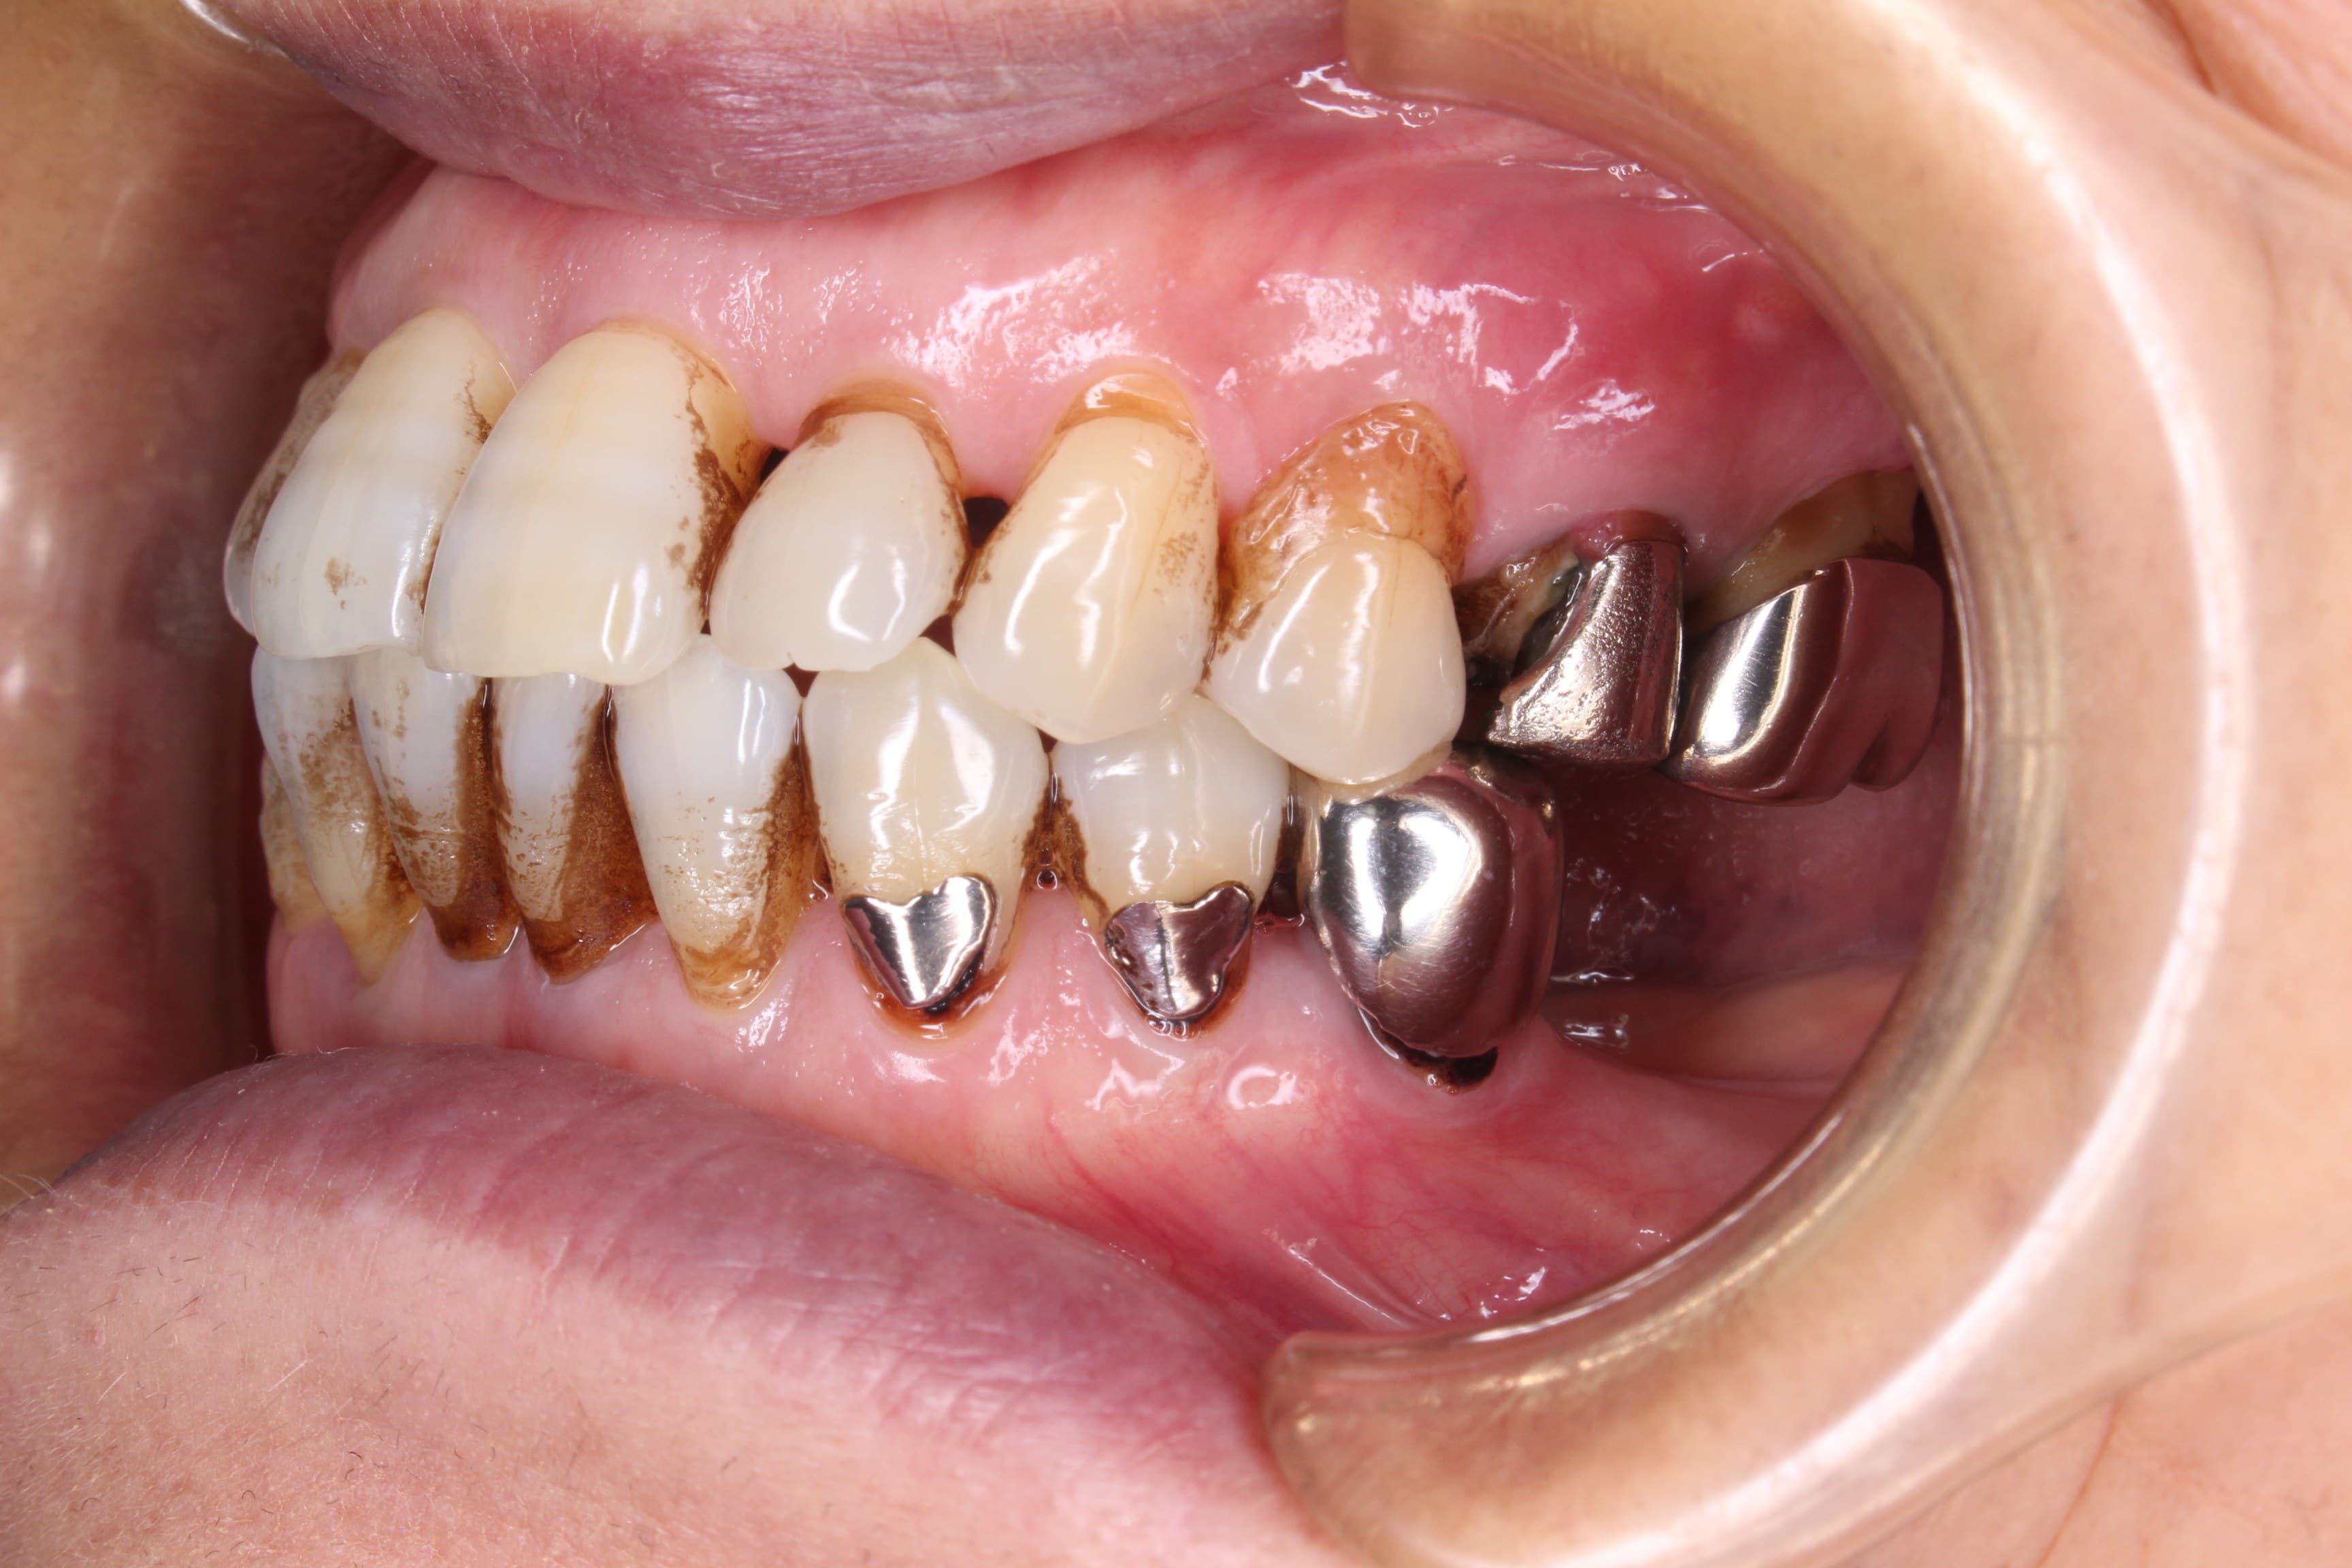

今回ご紹介する歯周専門治療のケースは、70代女性の方です。

最近奥歯が折れた事をきっかけに来院されました。

初診時

初めてお会いした時、これまでは痛い時しか歯科医院へ行くことはなかったそうで、本当は嫌だけど歯は悪くなったら抜くものだと思っていらっしゃいました。

幸いにも、まだ前歯部は多く残っており今から予防の為の治療をすれば、現状の維持が可能であることをお伝えして、歯周専門治療を行うこととなりました。